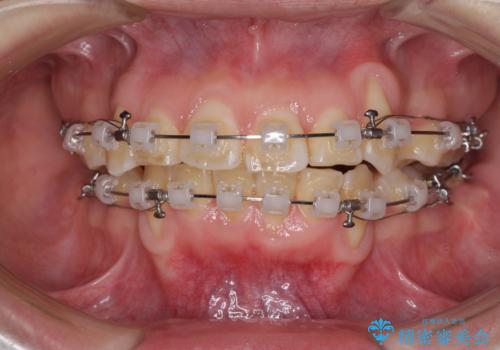

- クリアブラケット

- 2年1ヶ月

- 10-30回